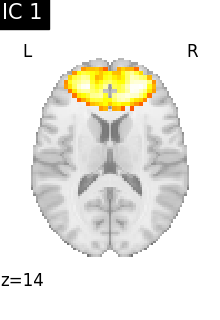

Finally, we plot the map for each ICA component separately

from nilearn.image import iter_img

from nilearn.plotting import plot_stat_map, show

for i, cur_img in enumerate(iter_img(canica_components_img)):

plot_stat_map(

cur_img,

display_mode="z",

title=f"IC {int(i)}",

cut_coords=1,

colorbar=False,

)